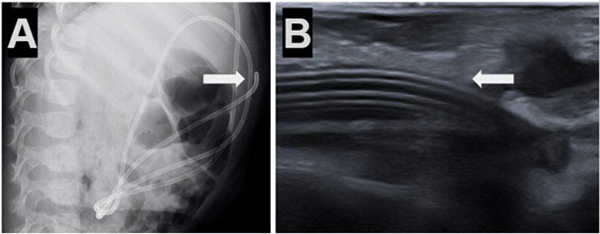

Caso 5. Paciente femenina de 1 año con antecedente de tumor de fosa posterior e hidrocefalia tratada con DVP al mes de vida, presentó episodios de vómitos y somnolencia con dilatación del sistema ventricular en comparación con estudios previos por tomografía simple de cerebro. Radiografías de sistema confirmaron migración subcutánea y retrógrada del catéter distal (Figura 5).

Figura 5. Caso 5: A) Se observa Rx de tórax y abdomen (perfil) con catéter distal a nivel abdominal con migración retrógrada. B) Ecografía abdominal: muestra ingreso y salida de catéter distal por mismo sitio; imagen típica de catéter en “doble caño” con signo ecográfico “caño de escopeta” (flecha blanca).